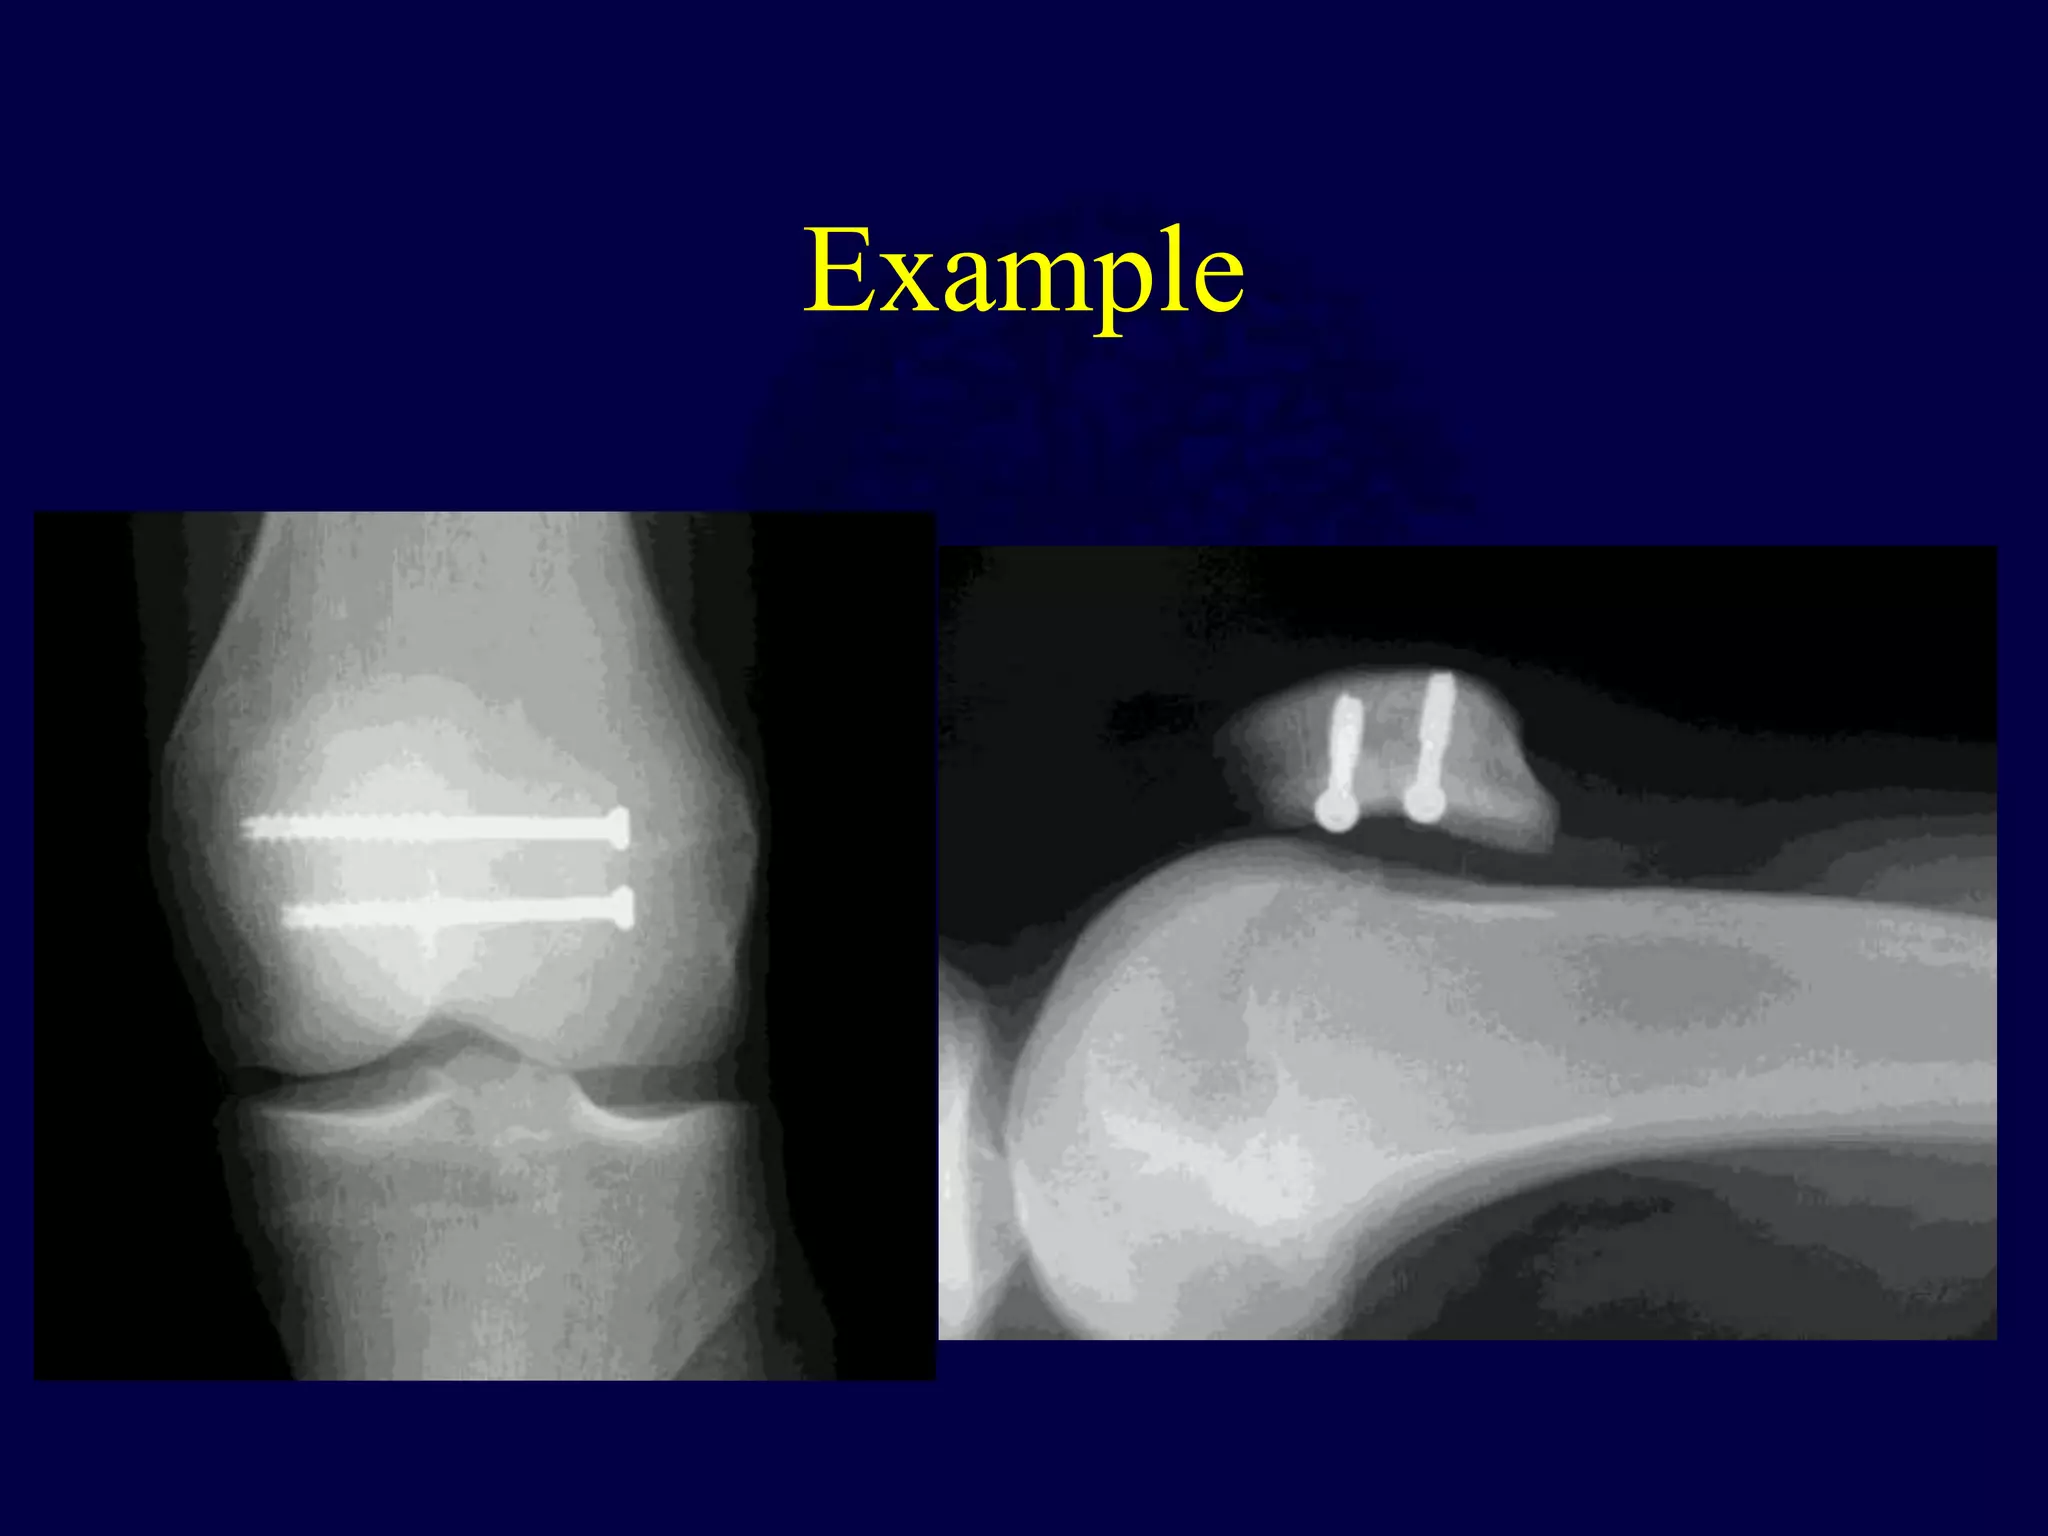

Lag-Screw Fixation

• Indicated for vertical

fractures

• Contraindicated for

extensive comminution

and osteopenic bone

Example